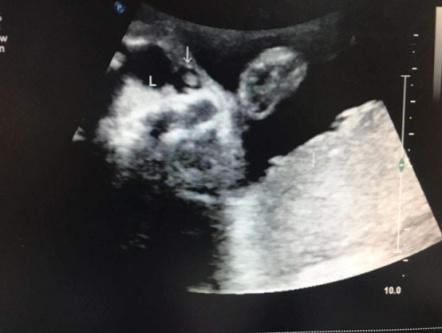

典型案例:孕妇,37岁,孕32周常规产检,系统检查胎儿及附属物,发现胎儿双侧眼眶内下方均可见一无回声区,大小分别约:右侧0.4x0.3cm、左侧0.8x0.7cm,边界清晰,内壁光滑,内透声好,左侧无回声内可见斑块状高回声,彩色多普勒检查其内未见血流信号,余未见异常;孕34周及36周随访复查,双侧无回声区消失。

鼻泪管囊肿的超声声像图为眼眶内下方的无回声区,内部可伴高回声,内部及周边无彩色血流信号,结合无回声区出现的时间,可以提示鼻泪管囊肿的诊断,但仍需与血管瘤、皮样囊肿等鉴别诊断。血管瘤多位于皮肤表面,多为实性回声或有分隔,内有较丰富的血流信号;皮样囊肿组织来源多样,内部成分复杂,超声表现多样,但表现为单纯囊肿者少见,另外皮样囊肿常发生于骨缝处,一般都发生在眼球外侧,发生于鼻侧者多位于鼻额骨缝处。